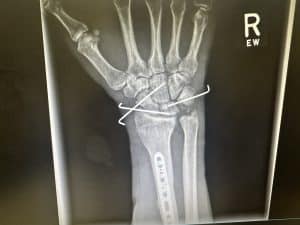

On Friday, March 29, I went to Dr. Guerrero in Southern California to get a check-up on my wrist. After seeing the x-rays, it makes sense why I am in so much pain. I did a number on it. The doctor said that the surgeon in Florida did a really good job, which was so great to hear! Everything looks really good. They ended up cutting out the stitches I had on the top and bottom of my hand. The pins in my wrist will stay in for a total of eight weeks. He decided to throw me in a hard cast and to come back to get that taken off and pull the pins out. After the pins come out, I can start therapy.

Following the accident, Devin was swiftly transported to a nearby hospital in Daytona for assessment and treatment. He underwent immediate surgery on his wrist to address the fracture. However, the need for surgery on his shoulder remains uncertain as medical professionals continue to evaluate his condition. As swelling subsides and Devin's healing progresses, doctors will gain a clearer understanding of the necessity for surgical intervention.